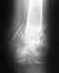

Мне 32 года, на работе неудачно упала и результат закрытый медиальный перелом шейки правой бедренной кости со смещением отломков.

04.10.2010 года по скорой помощи была доставлена в больницу, под местной анестезией наложено скелетное вытяжение правого бедра. 06.10.2010 под ЭТН выполнена операция: остиосинтез шейки правой бедренной кости конюлированными спонгиозными винтами ChM. 22.10.1010 была выписана домой в удовлетворительном состоянии, послеоперационных осложнений не было. 08.01.2011 была сделана R-графия тазобедренного сустава, по словам врача о консалидации перелома еще говорить слишком рано, опираться на ногу не разрешил, через 8 недель снимок повторить и тогда будет решено о нагрузке на ногу. Опять же по словам доктора сращение идет нормально, винты с места не сдвинулись...очень хотелось бы знать какие лекарства мне пить или какую терапию проводить чтобы избежать некроза шейки, мой доктор на эти вопросы не отвечает...нога подвижна, поднимается, сгибается, имеют место незначительные боли в паховой области и месте операции...чувствую инородное тело в...в детстве у меня был двухсторонний вывих тазобедренных суставов, последствий не осталось полностью вылечили без операции... заранее благодарна за ответ